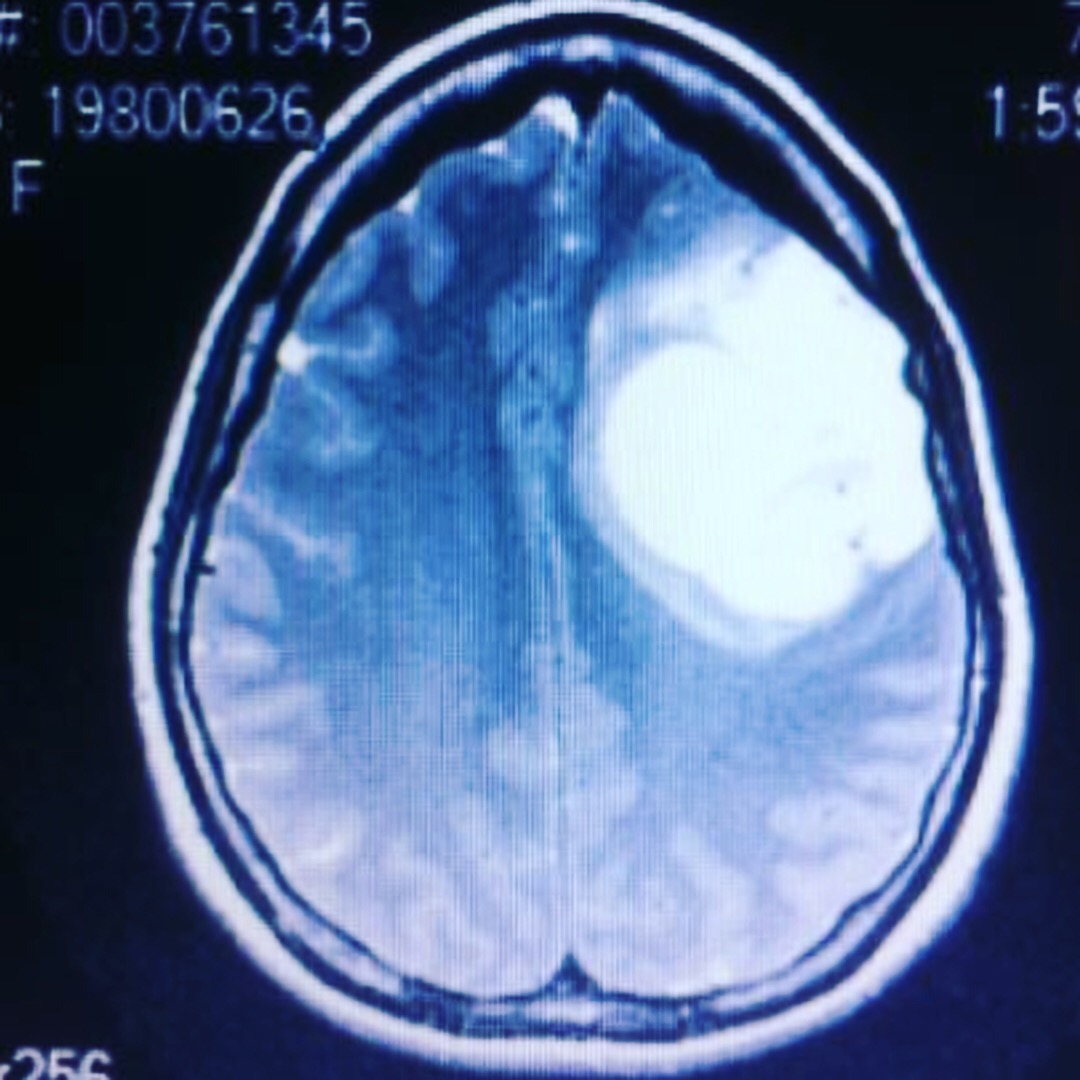

In 2013, six years ago this June, only months after Catherine gave birth to her second child, she began suffering from constant headaches and head pressure, which lead to an ER visit where they discovered she had a grapefruit sized, cancerous brain tumor.

Soon thereafter, doctors performed an awake craniotomy on her and removed most of the tumor. Catherine went through aggressive chemo and radiation and was given 2 -6 years to live.